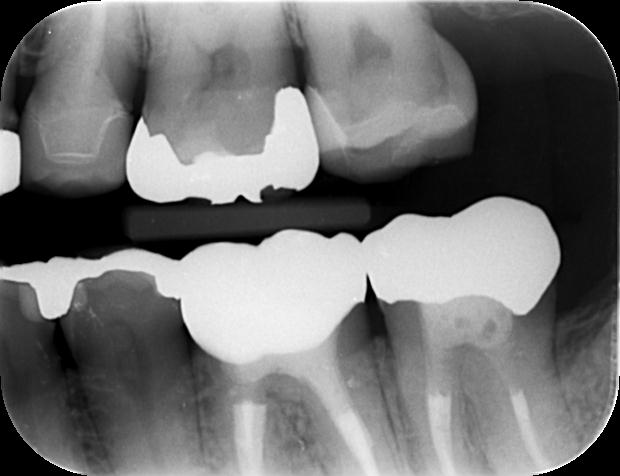

左下6番根管治療後のレントゲン写真です。

透過像は縮小しているようにも見えますが、残念ながら6番の治療のみではサイナストラクトの消失には至りませんでした。

左下6番の治療後に撮影したCT画像ですが病変の大きさが確認できます。

左下7番治療後のレントゲン写真です。

透過像は残存していますがサイナストラクトは消失いたしました。